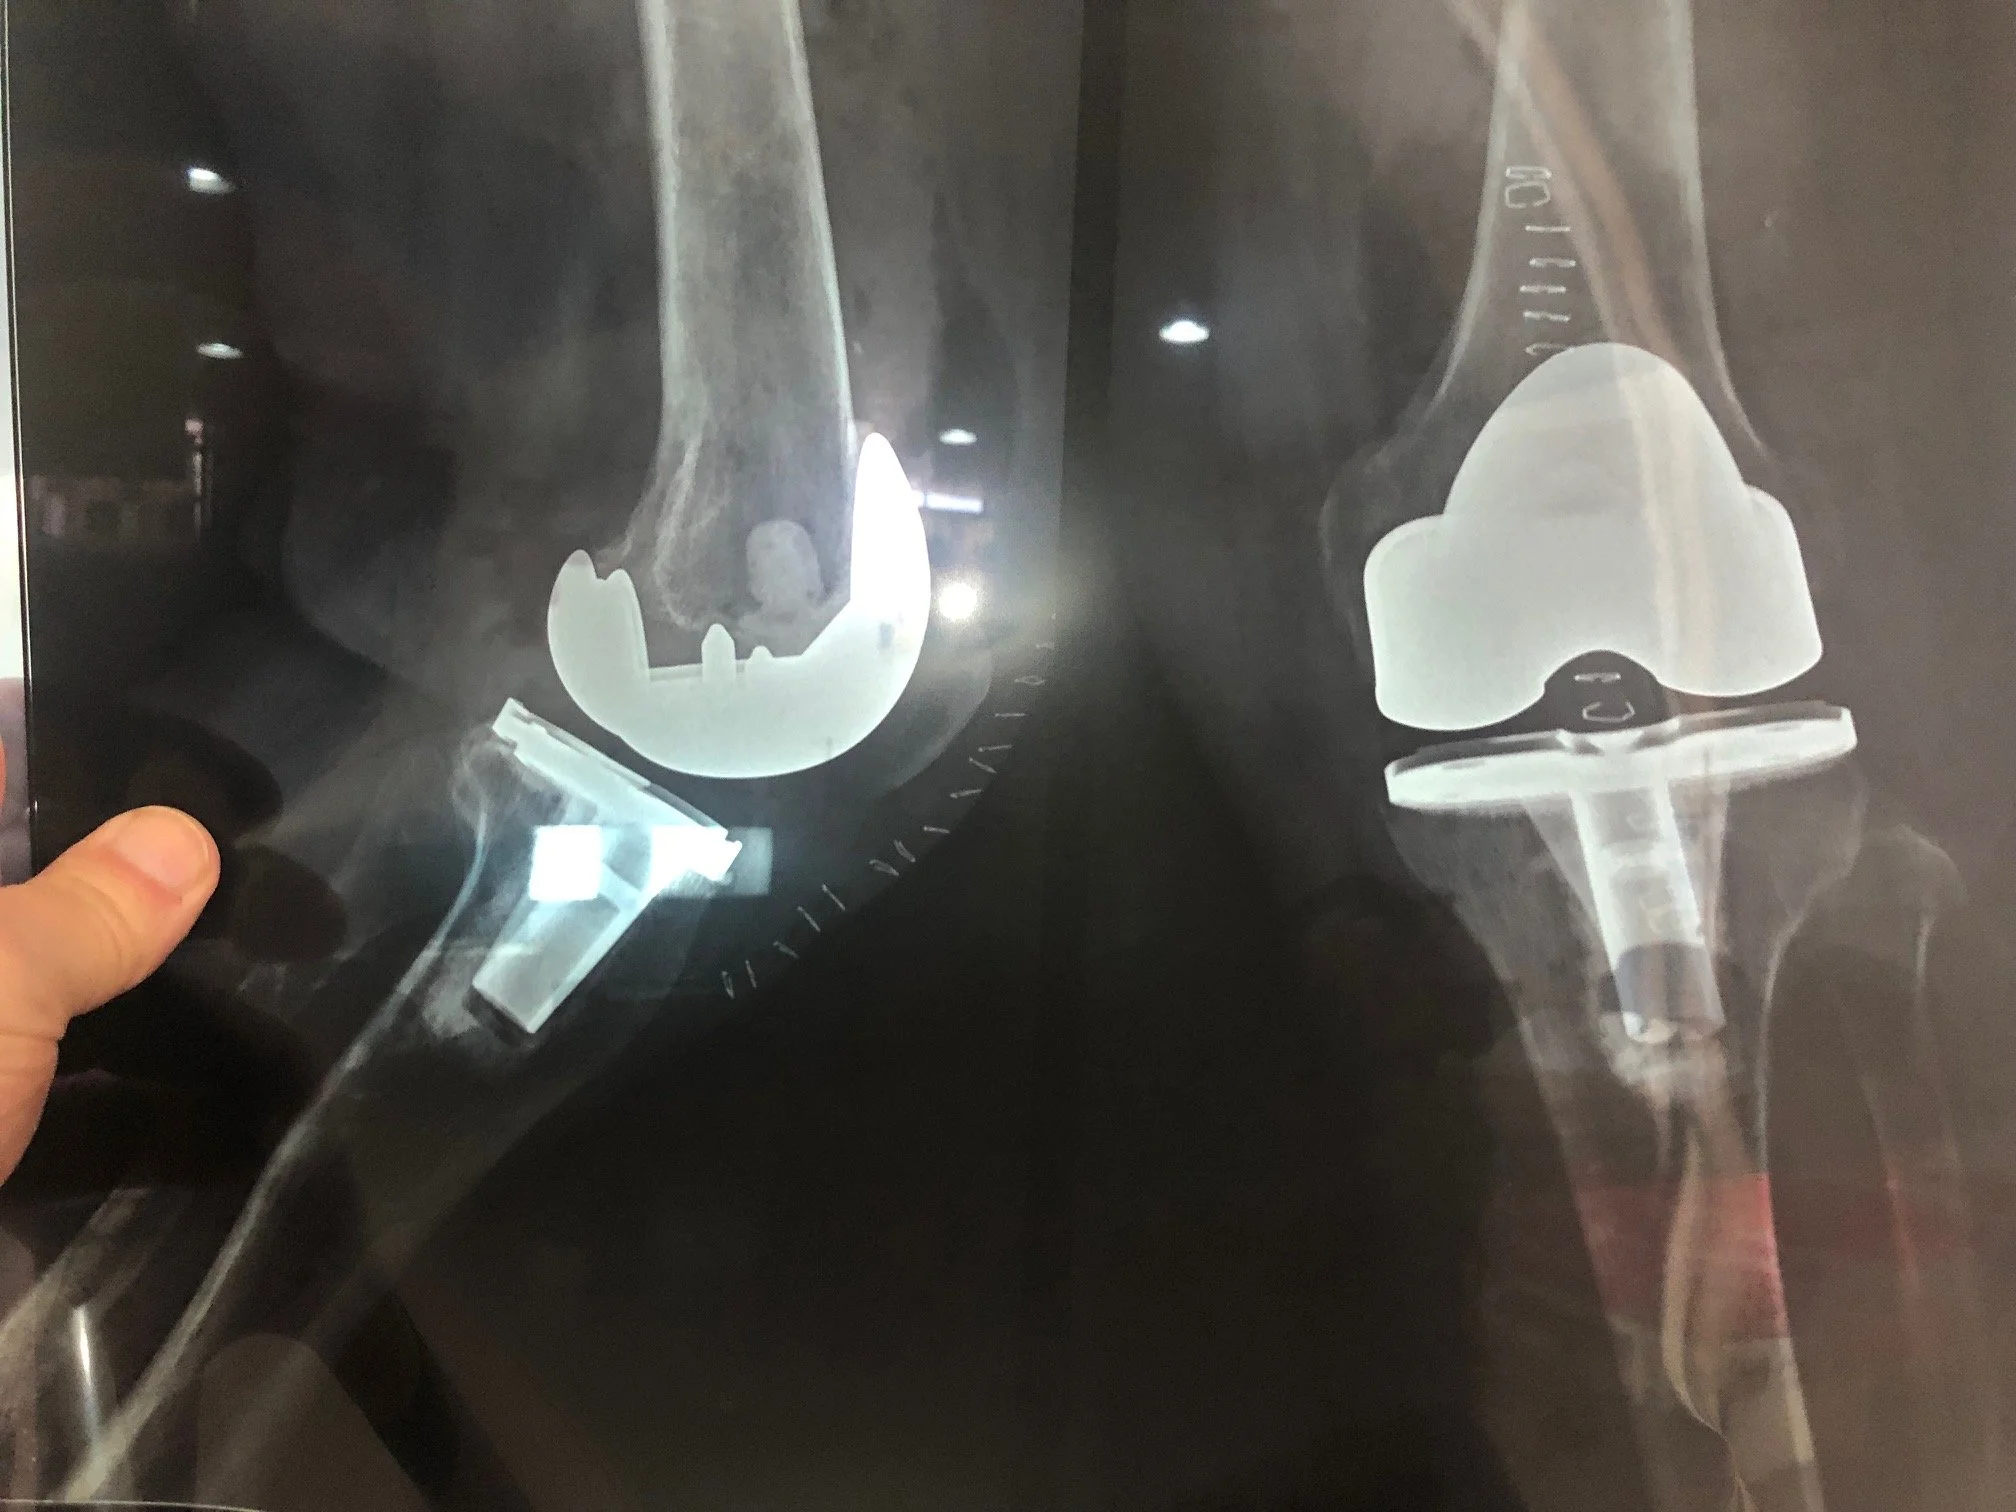

One notable knee patient was Juan, a 66 year-old farmer, who underwent primary knee replacement five years ago. One day on the farm, he slipped and fell, knocking his implants loose. After that, he continued his normal farming chores which further loosened and pushed his implants into unintended positions that rendered his knee more and more disabling. At the point when he needed to start using a cane during his farming work, he started to pursue medical help to fix his condition. He was told that he would need to purchase the revision knee implant for him to have his knee fixed. Even though he lived many miles from Antigua, he learned about Team Hope in Motion and that he would be able to receive his implant without any cost from Team HIM. After making the 8-hour journey to Antigua, Dr. Mike Berend performed revision knee surgery removing his existing implants which were malpositioned, creating toxic metal debris that was negatively affecting the muscles and tissue around his knee. A Zimmer Biomet NexGen CCK knee was installed along with Trabecular Metal augments to restore the anatomic position of his knee and allow him to walk normally again. From his hospital bed he spoke about how extremely grateful he was to have a new knee which will enable him to get back to farming and resume his life in a normal fashion.